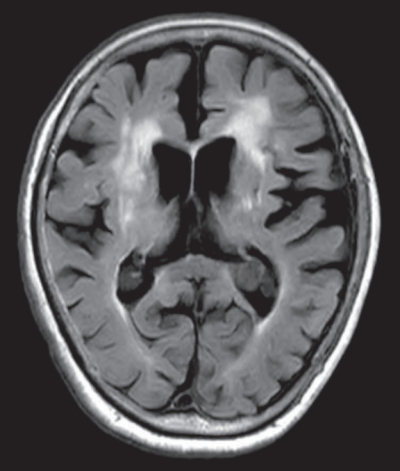

意識は清明。心拍数 82/分、整。血圧 154/82 mmHg。復唱は可能だが構音障害を認める。左顔面を含む左上下肢の不全片麻痺を認めた。来院時の頭部MRIの拡散強調像、FLAIR 像及び MRAを別に示す。